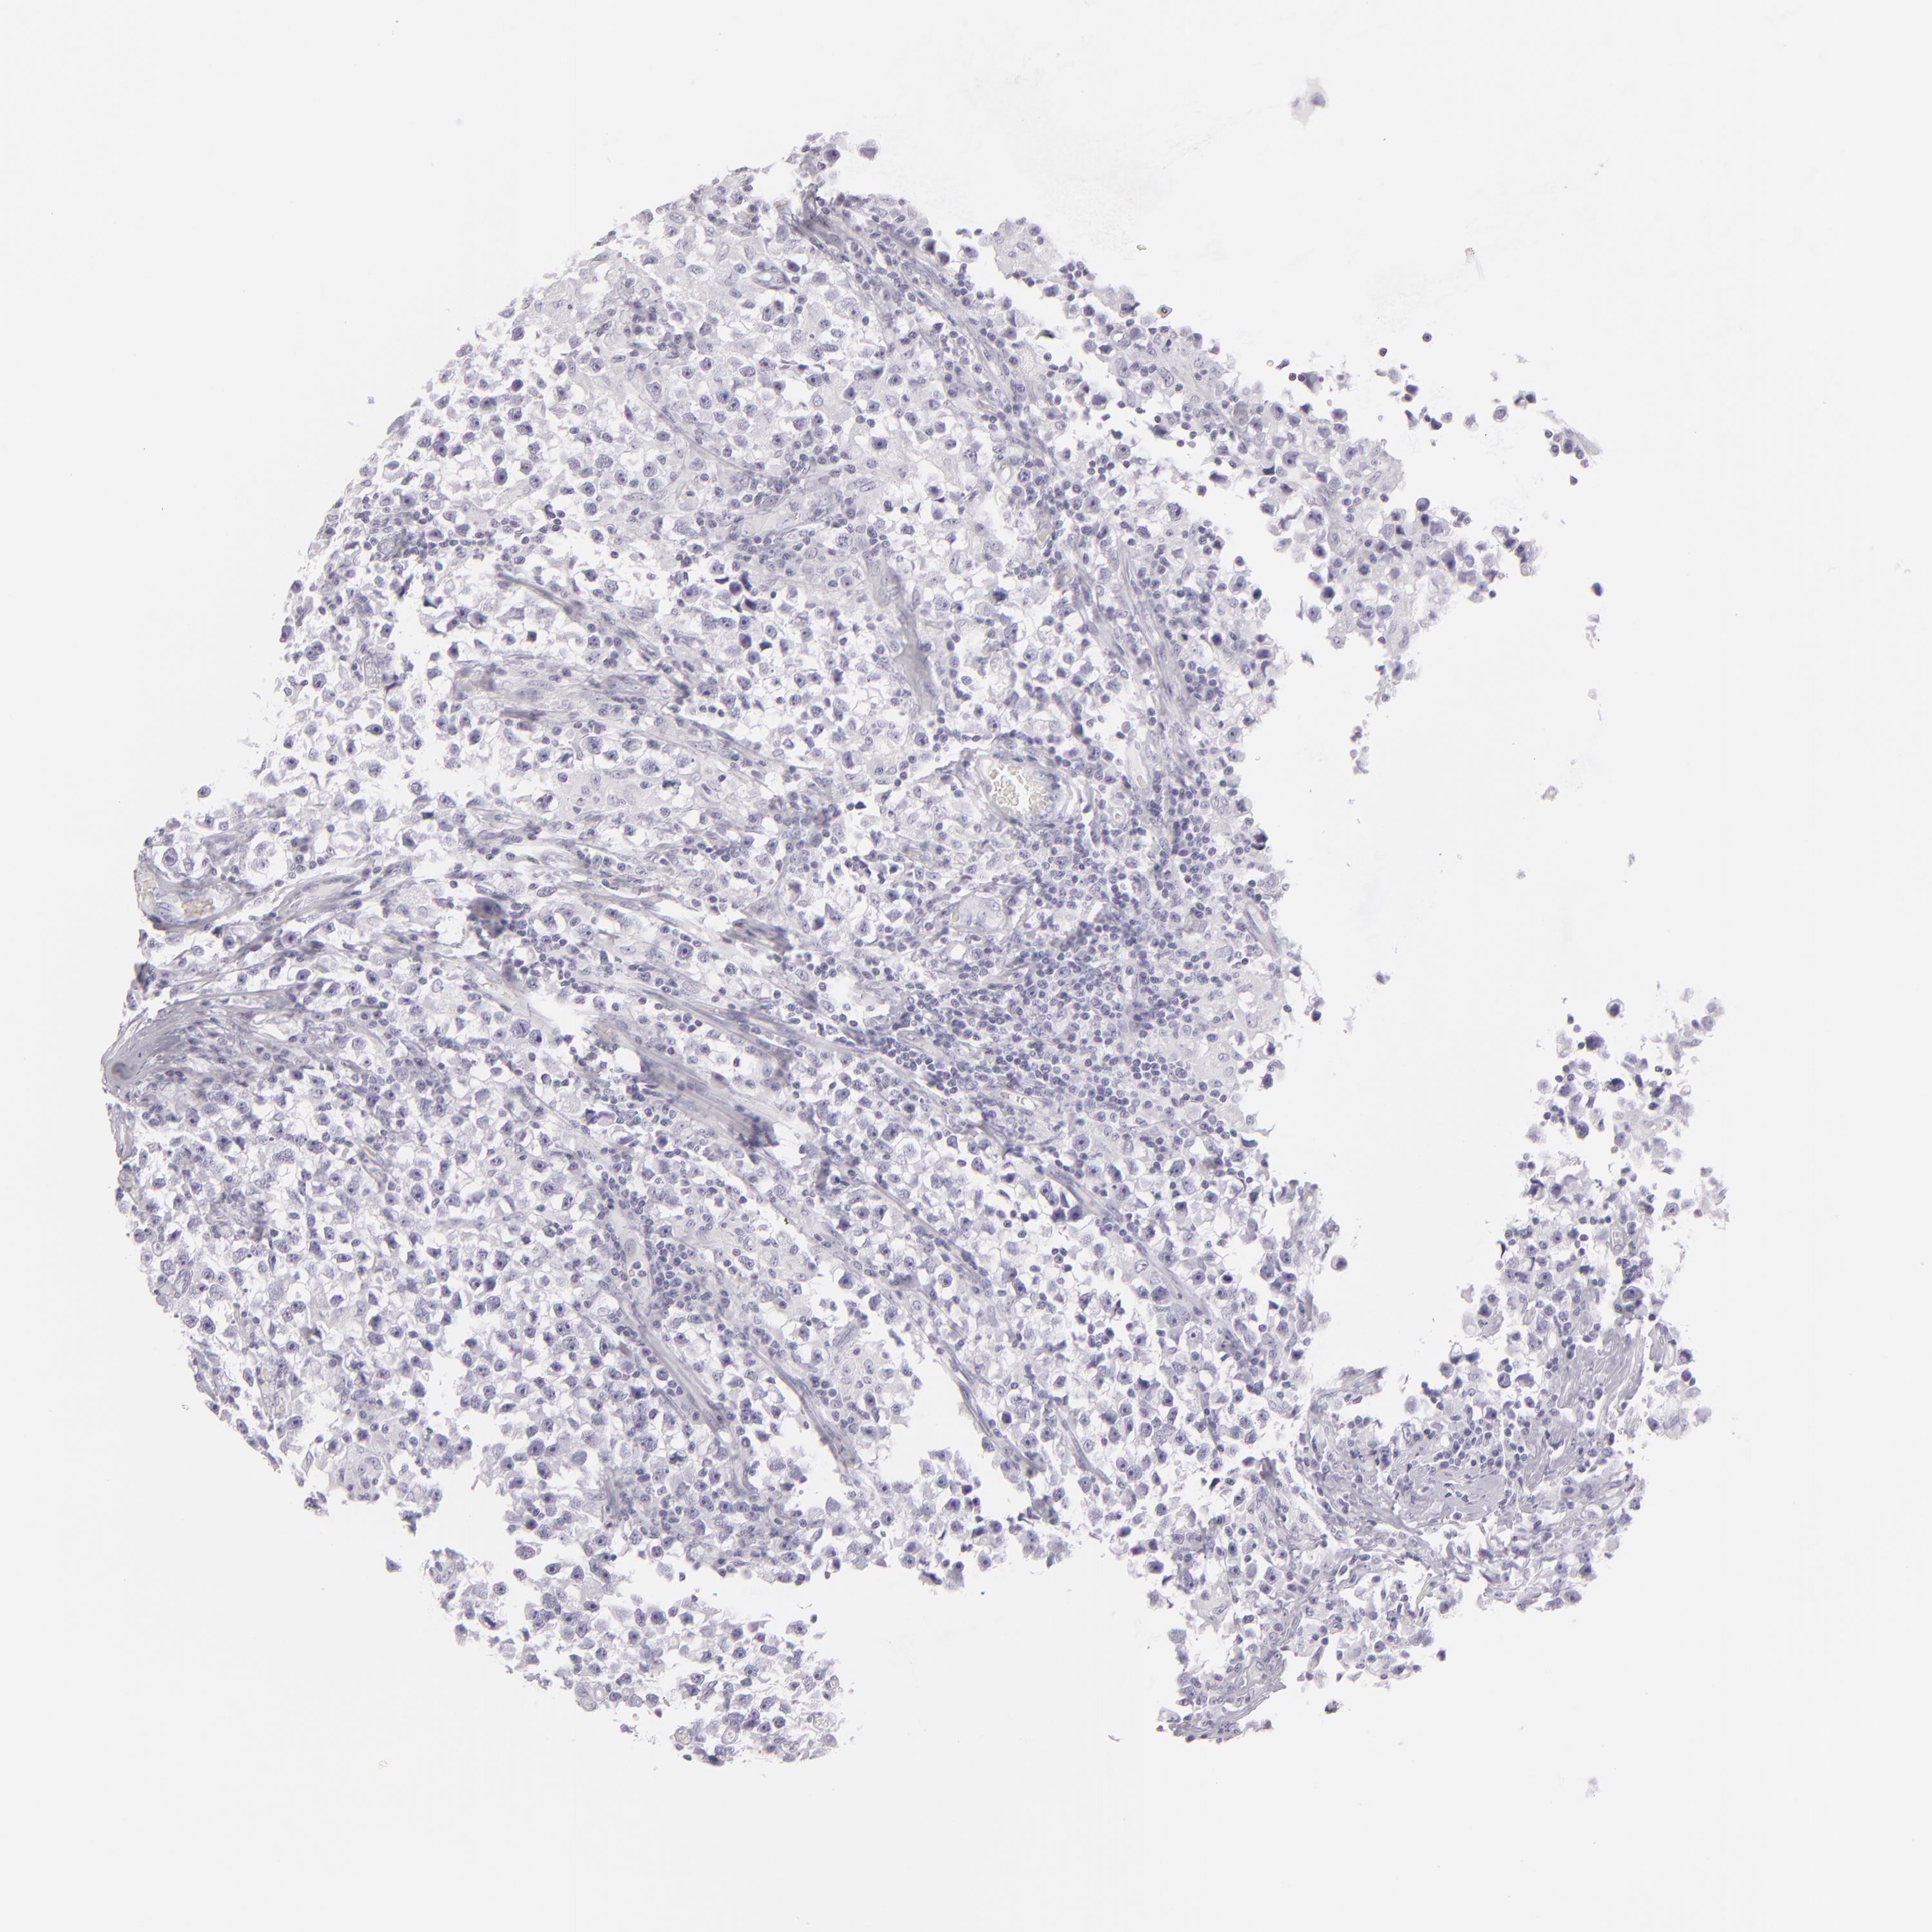

TESTIS CANCER - Protein expressioni

A mouse-over function shows sample information and annotation data. Click on an image to view it in a full screen mode. Samples can be filtered based on level of antibody staining by selecting one or several of the following categories: high, medium, low and not detected. The assay and annotation is described here.

Note that samples used for immunohistochemistry by the Human Protein Atlas do not correspond to samples in the TCGA dataset.

Antibody stainingi

Antibody staining in the annotated cell types in the current human tissue is reported as not detected, low, medium, or high, based on conventional immunohistochemistry profiling in selected tissues. This score is based on the combination of the staining intensity and fraction of stained cells.

Each image is clickable and will lead to virtual microscopy that enables deeper exploration of all samples and also displays staining intensity scores, fraction scores and subcellular localization as well as patient and tissue information for each sample.

Antibody HPA030188

Antibody HPA030189

Carcinoma, Embryonal, NOS

Seminoma, NOS